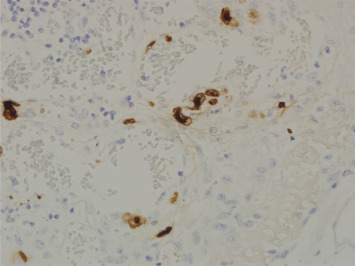

An emergency operation was performed, and multiple perforations from the ascending colon to the rectum, significant pus debris at the peritoneum, and massive dirty ascites were discovered. Amebic trophozoites (Fig. 5), CMV inclusion bodies (Fig. 6), and fungal hyphae (Fig. 7) were identified in the resected colon specimen. Broad-spectrum antibiotics with an antifungal agent were prescribed. Serum tests showed positive IHA for amoeba, and a CMV viral load of 272,000 cp/mL. The ascites culture yielded Enterococcus faecium, Candida albicans, and Candida krusei. The pleural effusion culture yielded Aspergillus fumigatus. Despite aggressive medical treatment, his condition deteriorated gradually, and he passed away about 10 weeks after admission.

Figure 5. Microscopic view of the resected specimen showing amebic trophozoites at the site of the colon ulcers. |

Figure 6. Cytomegalovirus inclusions are observed in capillary endothelial cells and confirmed by CMV immunostaining. |

An endoscopic finding of HIV enteropathy may mimic the features of IBD and lead to misdiagnosis. In patients with advanced HIV infection, CD4 T-cell count depletion and opportunistic infections (OIs) occurs. OIs include bacterial, viral, fungal, and protozoan infections. CMV is the most common opportunistic pathogen in HIV-infected patients and can involve the whole gastrointestinal (GI) tract. Eosinophilic nuclear inclusions are characteristic of CMV-infected cells and are usually found in stromal and endothelial cells [6]. Entamoeba histolytica infections are usually asymptomatic; however, in immunocompromised patients, invasive amebiasis has mostly presented as colitis and liver abscesses. The trophozoite invades the colonic mucosa and spreads to the extra-intestinal organs. Endoscopy is useful in diagnosing amebic colitis, since amebic trophozoites can be detected from the biopsy [7]. The most common fungal infection in immunocompromised patients is candidal esophagitis; however, enteric fungal infections are unusual, even in HIV-infected patients. The diagnosis was based on fungal hyphae noted in the biopsy specimen. Highly active antiretroviral therapy (HAART) decreased the incidence and prevalence of OIs.